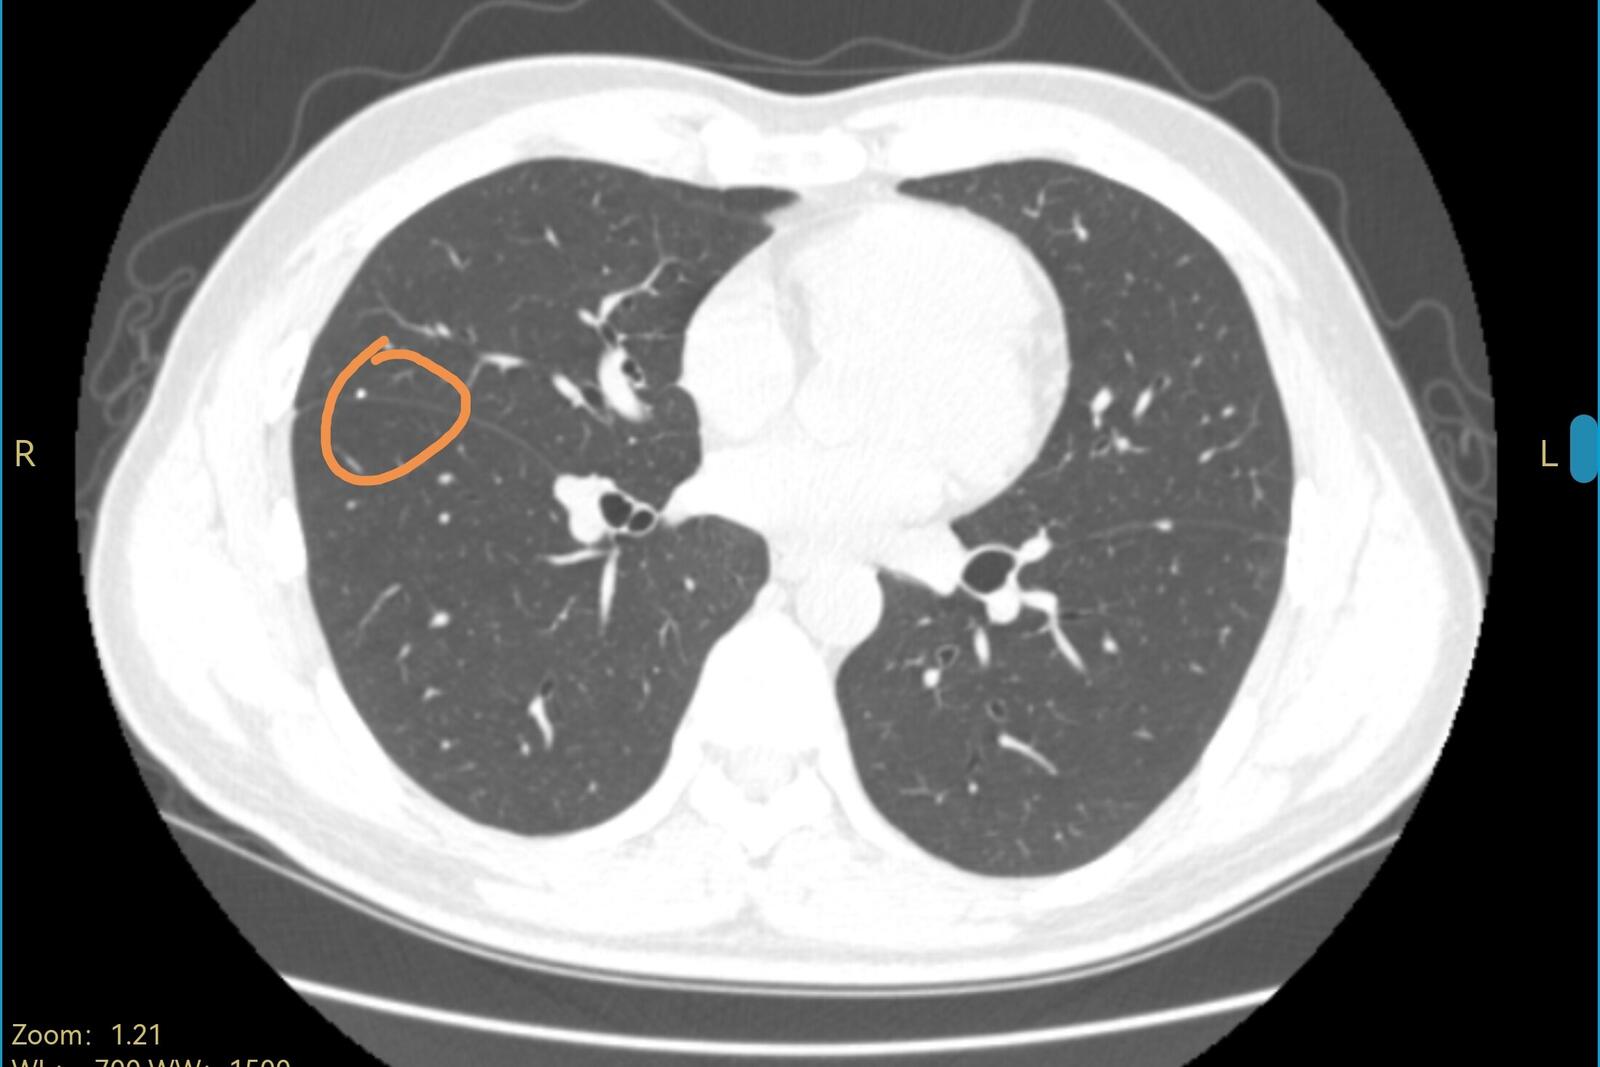

我看到了他的电脑图像,肺里面这两个结节,一左一右,都是在叶裂之间,直径都很小,右边那个结节是有钙化的,左边那个结节虽然没有钙化,但看起来像是个肺表面的淋巴结,这两个结节都考虑是良性,可以继续观察。CT上也没有其他可以解释胸口疼的表现,我请他再观察一下,也许不知道是怎么样抻了一下引起的疼痛。